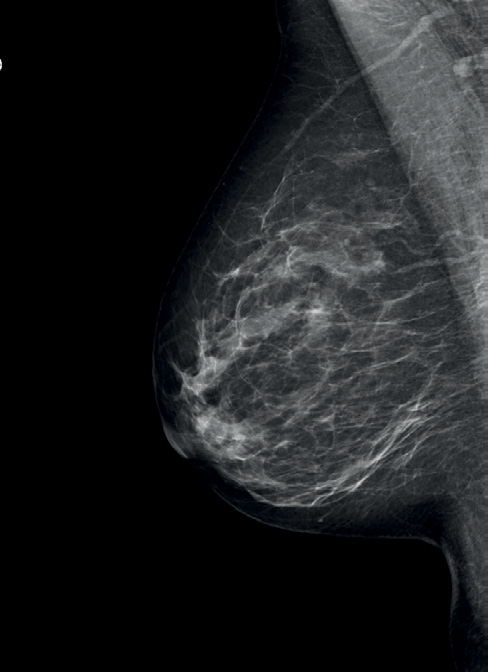

Mammographie-Aufnahme

Die digitale Vollfeld-Mammographie ist das Standardverfahren in der Brustdiagnostik. Sie ist die einzige Methode, um Mikro-Verkalkungen erkennen zu können, die nicht selten Vorstufen von Brustkrebs darstellen.

Die Mammographie ist eine Röntgenuntersuchung.

Bei der Mammographie muss die Brust für die Aufnahme komprimiert werden, einerseits um qualitativ hochwertige Aufnahmen zu erstellen, andererseits um die Strahlenbelastung soweit wie möglich zu reduzieren.